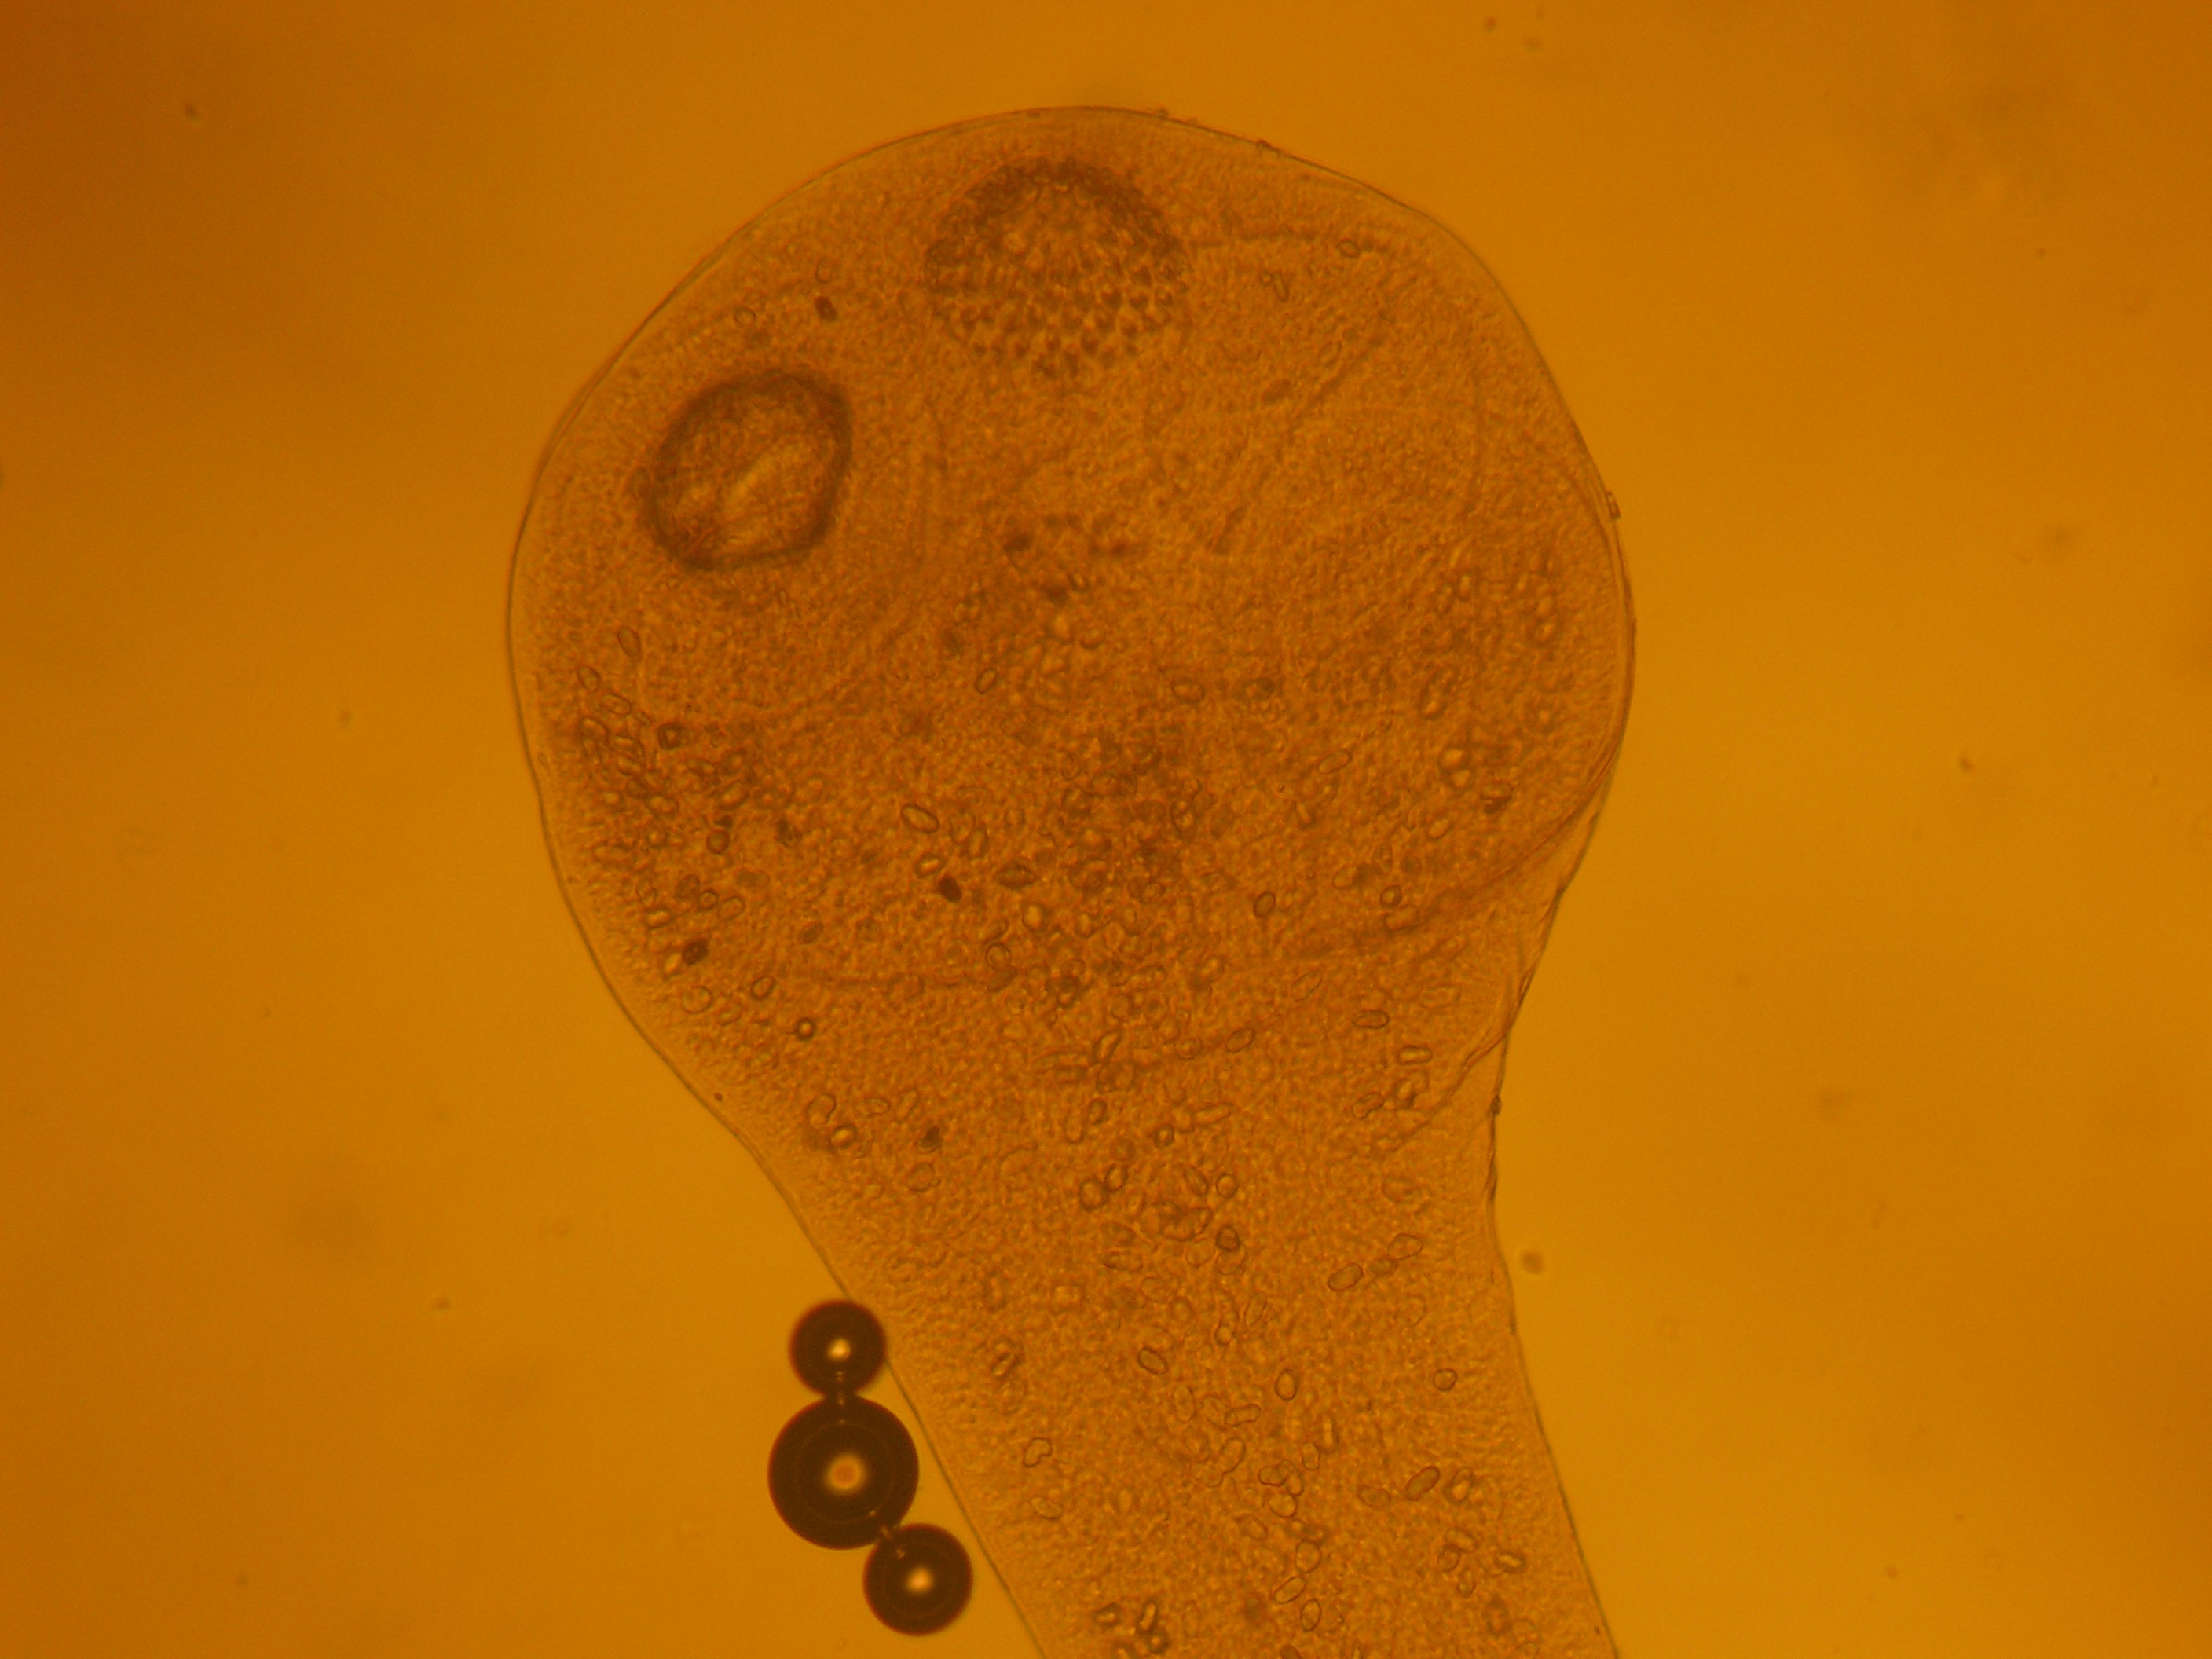

При дослідженні безпритульних собак біотичного центру ХДЗВА встановлена ураженість собак гіардіозом (Рис. 13-15).

Екстенсивність гіардіозної інвазії складала 55,7%, при кількості цист у полі зору мікроскопу від 1 до 8.

Рис. 14. Трофозоїти гіардій (фарбування розчином Люголя).